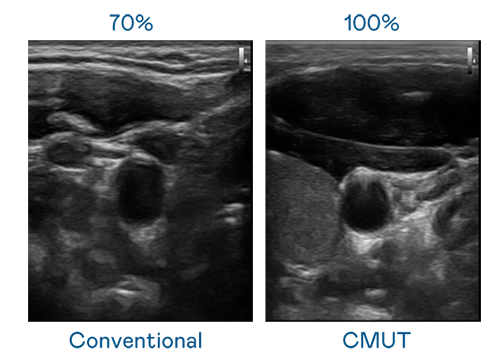

CMUT 技术是一种用电容式微机电元件来产生超音波讯号的技术。与传统 PZT 压电式技术相比,CMUT 频宽增加 30%,更宽频的超音波讯号让影像解析度大幅提升,是实现高影像品质医疗超音波扫描、促进精准医疗发展的关键技术。

大频宽带来超清晰影像

超音波影像的解析度高低,首先取决于探头能发出的讯号频宽。利来国际w66 CMUT 可提供高清晰的超音波讯号,提供高频宽、高灵敏度、影像纹理细节更高的超音波影像,协助医护人员缩短影像判读时间及利用精准的医疗影像进行诊断。